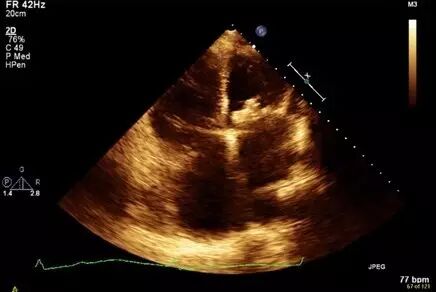

图1 短轴切面显示,主动脉小叶边缘增厚阻碍了主动脉瓣正常开闭